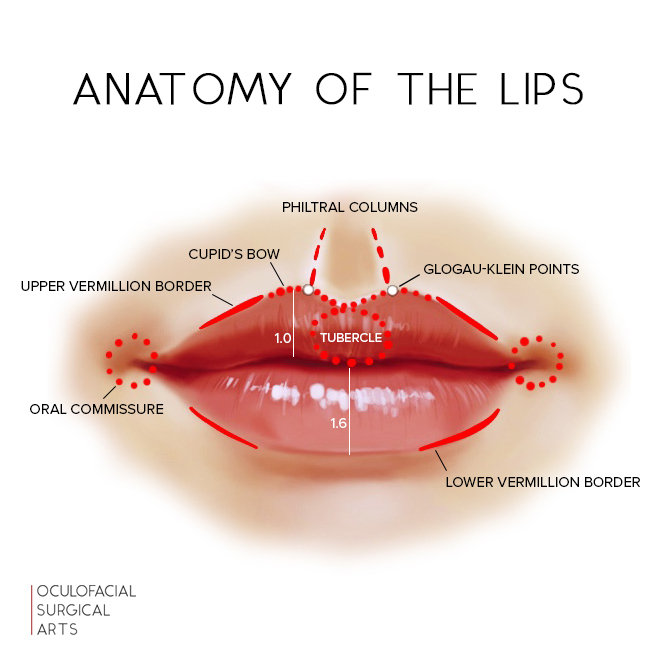

Anyways, you’ll typically want to inject into the vermillion border or vermillion body of your lips, this helps shape your lips & add volume.

Microdroplet injections into the aforementioned areas is standard. But if you’re considering doing this, do your own research & analyze filler techniques for lips, injecting fat is fairly similar.

Anyways, you’ll typically want to inject into the vermillion border or vermillion body of your lips, this helps shape your lips & add volume.

Microdroplet injections into the aforementioned areas is standard. But if you’re considering doing this, do your own research & analyze filler techniques for lips, injecting fat is fairly similar.